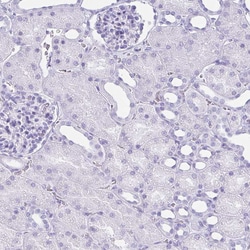

Invitrogen™ ATP4B Polyclonal Antibody

Immunogen sequence: TPDYQDQLRS PGVTLRPDVY GEKGLEIVYN VSDNRTWADL TQTLHAFLAG YSPAAQEDSI NCTSEQYFFQ ESFRAPNHTK FSCKFTADML Highest antigen sequence indentity to the following orthologs: Mouse - 83%, Rat - 80%.

| Immunohistochemistry (Paraffin) | |